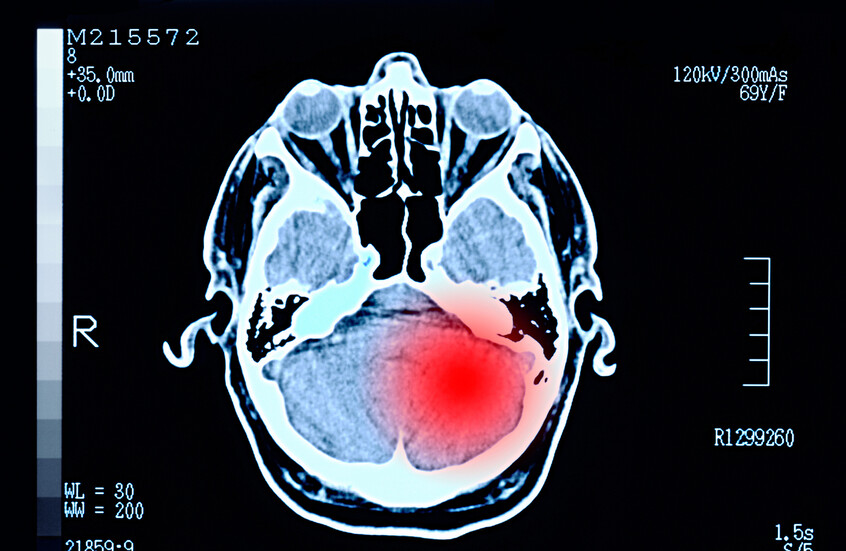

"كوفيد الطويل الأمد" والخرف المبكر.. تحذيرات من علاقة محتملة مثيرة للقلق!

كشف فريق من علماء الأعصاب في الولايات المتحدة عن علاقة جديدة بين الإصابة بفيروس "كوفيد-19" وبعض التغيرات العصبية لدى فئة معينة من المرضى.

وحذّر العلماء من أن الإصابة بـ"كوفيد-19"، وخاصة الحالات التي تترافق مع أعراض طويلة الأمد، قد تزيد خطر الإصابة بالخرف المبكر لدى البالغين، حتى قبل بلوغ سن السبعين.

وأوضح الدكتور غابرييل دي إيراوسكوين، أستاذ طب الأعصاب في جامعة تكساس هيلث سان أنطونيو، أن الأشخاص فوق سن 57 عاما ممّن أُصيبوا بـ"كوفيد الطويل الأمد" أظهروا خصائص شبيهة بأعراض ألزهايمر في مراحله الأولى.

وأكد في تصريح لصحيفة "وول ستريت جورنال" أن هذه التغيرات "لا تبدو قابلة للعكس لدى كبار السن".

كما يجري الدكتور إيراوسكوين دراسة موسعة شملت 4000 مريض أصيبوا بـ"كوفيد" بعد بلوغهم الستين. وتشير بياناته الأولية إلى أن نحو ثلث المرضى الذين تجاوزوا سن 65 عاما ويعانون من أعراض طويلة الأمد، يستوفون معايير ما يعرف بضعف الإدراك الخفيف (حالة تسبق عادة تطور الخرف).

وتظهر الإحصاءات أن خطر الإصابة بالخرف الكامل يرتفع إلى السدس في غضون عام واحد لدى المصابين بضعف الإدراك الخفيف.

هل تزيد عدوى "كوفيد-19" من خطر الإصابة بألزهايمر؟

وتتوافق هذه النتائج مع مجموعة متزايدة من الدراسات التي تربط بين "كوفيد" والخرف. فقد أفاد تقرير حكومي بريطاني سابق بأن أكثر من نصف المصابين بـ"كوفيد الطويل الأمد" يعانون من مشاكل في التركيز والذاكرة.

كما وجدت دراسة أُجريت على قرابة مليون مريض أن ثلثي الأشخاص فوق سن 65 عاما، ممّن دخلوا المستشفى بسبب "كوفيد"، تعرضوا لتدهور إدراكي ملحوظ.

ورغم أن السبب الدقيق لا يزال قيد البحث، يتساءل العلماء ما إذا كان الفيروس يسبب تغيرات عصبية تؤدي إلى الخرف، أو ما إذا كان يسرّع تفاقم أمراض دماغية موجودة مسبقا.